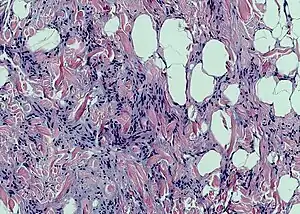

Spindle cell lipoma

Spindle cell lipoma is an asymptomatic, slow-growing subcutaneous tumor that has a predilection for the posterior back, neck, and shoulders of older men.[1]: 625 [2]